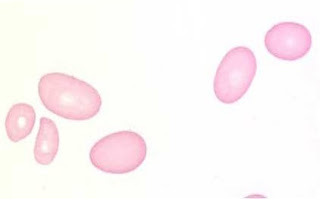

ERITROCITOS:

Los eritrocitos, (también llamados glóbulos rojos ohematíes), son los elementos formes cuantitativamente más numerosos de la sangre. La hemoglobinaes uno de sus principales componentes, y su objetivo es transportar el oxígeno hacia los diferentes tejidos del cuerpo. Los eritrocitos humanos carecen de núcleo y de mitocondrias, por lo que deben obtener su energía metabólica a través de la fermentación láctica. La cantidad considerada normal fluctúa entre 4.500.000 (en la mujer) y 5.000.000 (en el hombre) por milímetro cúbico (o microlitro) de sangre, es decir, aproximadamente 1.000 veces más que los leucocitos.El exceso de glóbulos rojos se denomina policitemia y su deficiencia se llama anemia.